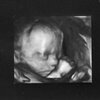

Jestem już po usg wszystko w porządkuDzidzia waży 360g, wszystkie narządy prawidłowe. Nie dało się jedynie super dokładnie ocenić serduszka, bo dzieciątko było plecami do mojego brzucha. Czyli kręgosłup maleństwa rzucał cień na serduszko. Musiałam skakać i przewracać się z boku na bo niestety maluch się nie odwrócił. Jednak są cztery jamy i wszystkie potrzebne naczynia. Za miesiąc mamy przyjść na podglądnięcie serducha.Potwierdza się termin porodu wyliczony wg pierwszego usg czyli 28 listopada.

No i najważniejsza informacja to jest DZIEWCZYNKA!!!!!!!